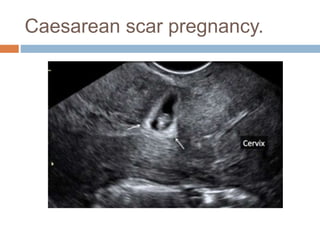

Caesarean scar pregnancy.